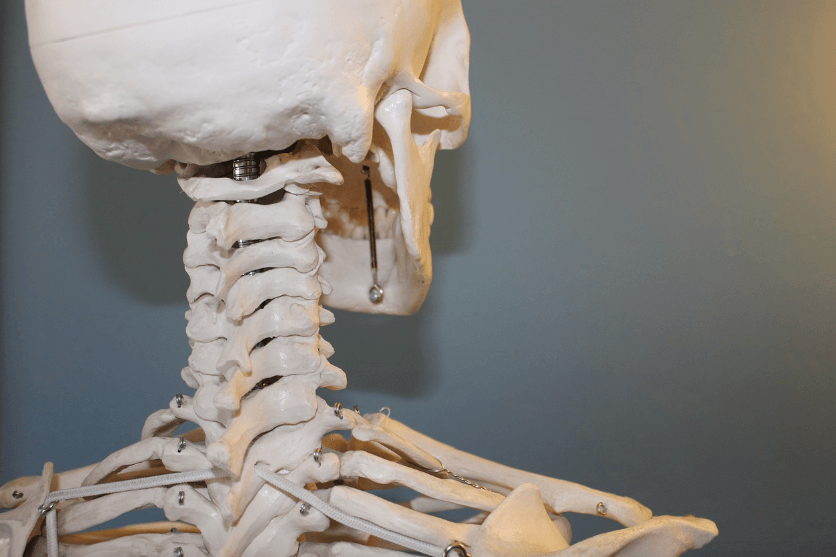

콘드로이친이란 그리스어로 '연골'을 의미합니다. 관절 건강에 중요한 성분으로, 연골이나 뼈, 힘줄 안에 존재하는 물질입니다. 연골은 우리 몸에서 관절을 보호하고 유연성을 유지하는 중요한 역할을 합니다.

2) 연골 보호 및 재생 지원 연골은 우리 관절의 충격 완화제 역할

콘드로이친은 연골 조직의 수분을 유지하고, 연골 세포의 성장을 촉진하는 데 필요한 영양소를 제공합니다. 이는 연골이 손상되는 것을 방지하고, 이미 손상된 연골의 회복도 돕는 중요한 역할을 합니다.